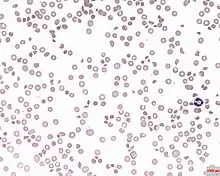

A picture of the blood under a microscope showing thrombocytopenia

Blood under a microscope showing thrombocytopenia